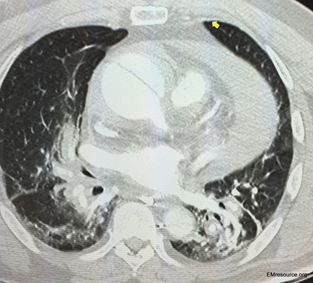

The patient with hypertension and syncope had cardiac tamponade. Causes, symptoms, and treatment described here.

A man with a history of hypertension had syncope and felt “sweaty.” Chest x-ray was normal. What’s your next test?